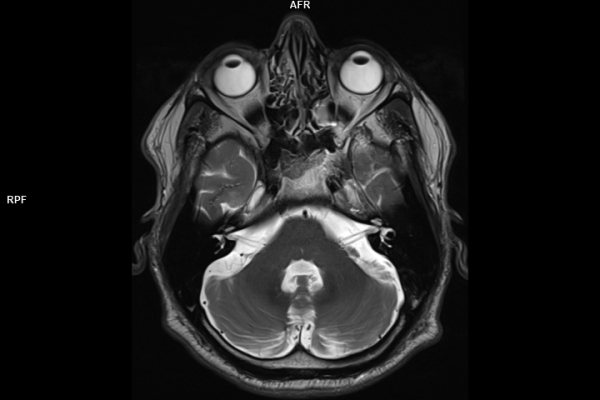

Detailbild MRT

Die MRT (Magnetresonanztomographie) arbeitet mit Magnetfeldern und Radiowellen und eignet sich besonders für Untersuchungen der Weichteile wie Gehirn, Muskeln oder Gelenke. Die CT (Computertomographie) nutzt Röntgenstrahlen und liefert schnelle, hochauflösende Bilder, insbesondere für Knochen, Lunge oder innere Organe. Die Wahl der jeweiligen Untersuchung richtet sich an das individuelle Krankheitsbild und wird bei der Überweisung festgelegt.